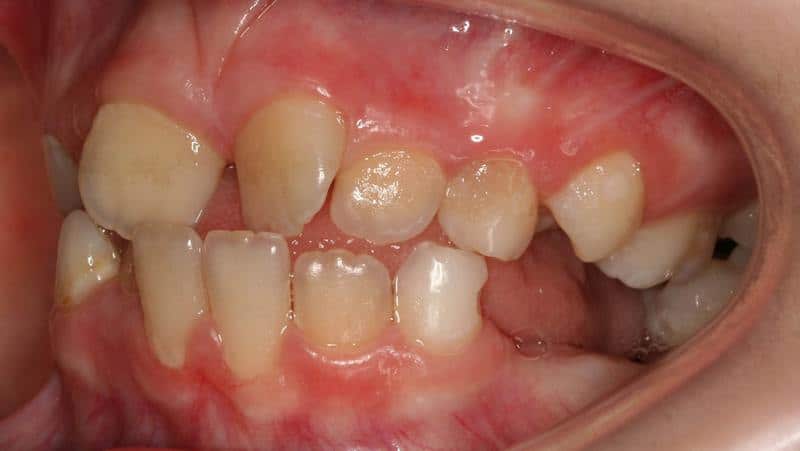

Макродентия характеризуется увеличенным размером коронковой части зубов. Этот тип отклонения гораздо опаснее для здоровья человека, чем микродентия. Состояние считается нормой только в том случае, если пациент имеет развитые челюстные структуры, в противном случае патология влечет за собой смещение единиц ряда и нарушение прикуса.

Стоматологи выделяют 2 вида макродентии: локализованную и генерализованную. При локализованном типе увеличено несколько элементов при генерализованной форме дефекта величина всех зубов превышает нормальные значения.

Макродентия – увеличенные зубы. Бывает у верхних резцов или боковых. Реже – на нижней челюсти, спереди. Превышение диагностируется при осмотре стоматологом, размеры его определяются при сравнении данных пациента со среднестатистическими. Оно может достигать диапазона 2–6 мм.

При диагностировании проверяют следующие размеры зуба: длину, ширину, высоту коронки. Ширина определяется измерением в самой широкой части зубного тела, высоту – от края десны пришеечной части до острого края или бугорка на жевательной поверхности. Макродентия на одной из челюстей вызывает диспропорции и нарушение прикуса.

Патологические размеры подразумевают слишком большие или слишком мелкие зубы. В первом случае налицо диагноз макродентия, который означает увеличенный размер коронки. Такая проблема приводит к трудностям с прорезыванием остальных «соседей», скученности и неправильному положению. Это косметическая патология, которая портит внешность. Лечение заключается в удалении и исправлении формы остальных зубов. Также проводится протезирование с целью закрытия дефектов.